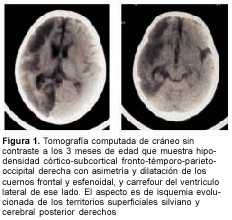

A los 3 meses de edad consultó por hemiplejia izquierda y retraso psicomotor. La tomografía computada (TC) de cráneo demostró un infarto hemisférico derecho (figura 1). Los estudios complementarios pusieron de manifiesto una coartación de aorta torácica descendente, sin evidencia de patología arterial sistémica. A nivel encefálico se estudió con angiografía de cuatro vasos de cuello, que demostró la existencia de una enfermedad de moyamoya (figuras 2 a 4). En ese momento no se consideró el tratamiento quirúrgico y una vez estabilizada se otorgó el alta. La coartación de la aorta no requirió cirugía y no se investigó el eventual nexo con la enfermedad de moyamoya. A los 8 meses de edad comenzó con hemiparesia derecha progresiva, lo que junto a su hemiplejia izquierda agravó su déficit motor severamente. Ingresó al Centro Hospitalario Pereira Rossell a los 10 meses. El examen del ingreso mostraba retardo neuropsíquico, hemiplejia izquierda espástica y hemiparesia derecha severa, que apenas vencía gravedad y no oponía resistencia. Una nueva TC mostró como elemento agregado al infarto derecho previo, una isquemia hemisférica izquierda (figura 5). Se resolvió realizar una revascularización quirúrgica del hemisferio izquierdo. Se intervino (figura 6) en el Servicio de Neurocirugía Pediátrica del Hospital. El procedimiento realizado fue una pialsinangiosis, con disección de la arteria temporal superficial izquierda con galea satélite y la sutura del tejido periarterial a la aracnoides temporal. La evolución posoperatoria fue buena, con recuperación progresiva de la función motora del hemicuerpo derecho. En forma gradual también comenzó a recuperar motricidad de su hemicuerpo izquierdo, anteriormente pléjico, y a mejorar sus performances, comenzando a pronunciar palabras a los cuatro meses, aunque manteniendo un retraso en el desarrollo psicomotor. Al año de operada se constató leve hemiparesia izquierda, ausencia de elementos deficitarios motores a derecha y persistencia de alteraciones en el lenguaje. Una ARM realizada a los diez meses de la operación mostró desarrollo de circulación colateral hacia el área quirúrgica (figura 7). Una TC de control permitió ver el infarto secuelar de hemisferio derecho y disminución franca de la hipodensidad del hemisferio izquierdo a los 18 meses de operada (figuras 8 y 9).

En una primera etapa, a los 3 meses de edad, la paciente fue encarada como un stroke en el lactante, y fue estudiada en ese sentido. Se fueron descartando las causas habituales hasta que se llegó al diagnóstico de enfermedad o síndrome de moyamoya con la angiografía. De acuerdo con las normas diagnósticas del cuadro 1, el caso debía ser catalogado como definitivo por la presencia de los ítems A y C. En ese momento no se consideró oportuno el tratamiento quirúrgico.